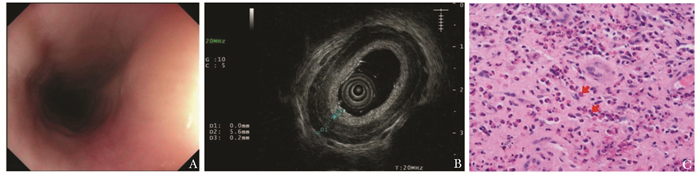

• 摘要: 本文报道一例因吞咽困难而就诊的嗜酸性粒细胞性食管炎病例。该患者为54岁女性,超声胃镜可见食管弥漫性增厚,病理示食管鳞状上皮内散在嗜酸性粒细胞浸润伴嗜酸性粒细胞微脓肿形成,嗜酸性粒细胞计数密度约为30个/HPF,符合嗜酸性粒细胞性食管炎的诊断标准(中度活动性)。口服醋酸泼尼松30 mg/d并逐步减量后,患者临床症状明显减轻,且影像学证实病变具有明显改善。本文总结该患者的诊疗经过并结合文献进行深入剖析,以期提升临床医生对该病的认知。

Abstract: This paper reports a case of eosinophilic esophagitis who presented with dysphagia. The patient was a 54-year-old woman with diffuse esophageal thickening on ultrasonographic gastroscopy. Pathology demonstrated scattered eosinophilic infiltration within the squamous epithelium of the esophagus, accompanied by eosinophilic microabscess, and the counting density of eosinophilic cells was about 30/HPF, which was consistent with the diagnostic criteria of eosinophilic esophagitis (moderately active). After oral administration of prednisone acetate 30 mg/d and gradual reduction of the dose, the patient's clinical symptoms were significantly eased, and the imaging confirmed the improvement of the lesions. This article summarizes the patient's diagnostic and therapeutic process, and reviews the relevant literature in order to enhance clinicians' understanding of this disease.